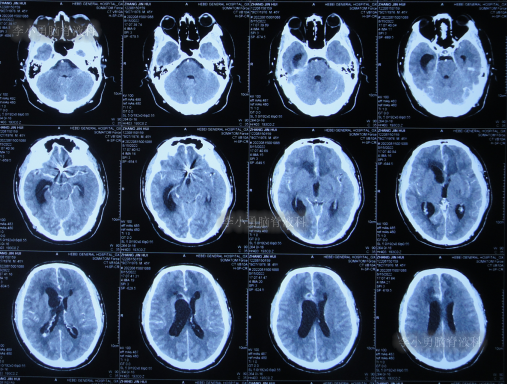

拔除引流管后10天即2022年7月25日(脑动脉瘤栓塞术后17天),查头颅CT示脑室周水肿,仍有少量积血(图-5);仍间断发热,且脑脊液白细胞仍高,脑脊液浑浊。

图-5:2022年7月25日头颅CT